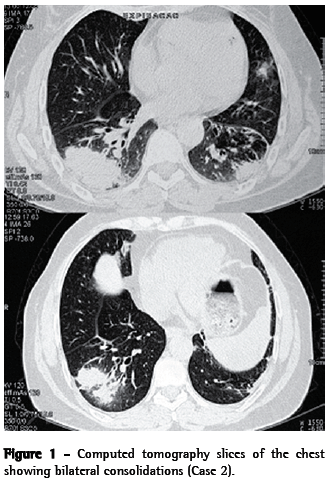

A 58-year-old female nonsmoker reported cough, moderate weight loss, fatigue and joint pain. The patient had a history of childhood asthma. After age 40, she experienced recurrence of the asthma-a fact that she attributed to contact with paints and solvents in the workplace. The patient used inhaled formoterol and budesonide (12/400 µg) daily, achieving satisfactory symptom control. A chest X-ray and a tomography scan of the chest showed bilateral consolidations and bronchiectasis in the lower lobes (Figure 1). Laboratory tests revealed the following: hematocrit, 41,1%; hemoglobin, 13.7 g/dL; leukocytes, 8,970, with lymphopenia (1,076 lymphocytes); ANF, present (1:160), with a dotted nuclear pattern; ESR, 56 mm/h; and C-reactive protein, 27.60 mg/L. At the time, Wegener's granulomatosis was suspected due to antineutrophil cytoplasmic antibody (ANCA) serum positivity. There was no upper airway involvement.

Cyclophosphamide treatment was started. In the first month, there was an increase in the left anterior cervical ganglion. The lymph node biopsy identified chronic granulomatous lymphadenitis with extensive noncaseating necrosis (Figure 2). Testing for AFB was negative. Since tuberculosis was suspected, the patient received the RHZ regimen for 6 months, presenting clinical involvement. However, in the following two years, the patient continued to experience fatigue, joint pain and well-defined episodes of pneumonia, as well as, during the final 6 months, oral lesion at the base of the tongue. She used systemic corticosteroids and antibiotics temporarily (5 to 6 times, for 10 to 14 days). With the worsening of the symptoms, the patient again sought treatment. Laboratory tests showed the following: ANF, 1:80 (homogeneous nuclear pattern); anti-DNA, nonreactive; lymphopenia; and ESR, 65 mm/h. A review of the anatomopathological diagnosis confirmed chronic granulomatous lymphadenitis with necrosis, numerous vacuolated histiocytes and giant Langerhans-type cells, as well as negativity for AFB and fungi. In addition, an immunohistochemical panel was performed, revealing CD68 (KP-1) positivity (xanthomatous histiocytes) and myeloperoxidase negativity, which is suggestive of KFD. The patient was then diagnosed as presenting a combination of KFD (which had gone undiagnosed for two years) and systemic lupus erythematosus (SLE). Her condition was controlled by the addition of oral azathioprine (100 mg/day) and prednisone (40 mg/day), the latter being tapered to discontinuation. Within 30 days, the patient presented clinical improvement, as well as improved laboratory test and tomography results.

Here, we have described two cases of KFD. The actual incidence of this disease is estimated to range from 0.5% to 5% of all cases of adenopathy analyzed histologically.(15) In a retrospective study of 1,724 lymph node biopsy samples, KFD was found in 36 cases.(16) Various infectious agents, such as Epstein-Barr virus, herpes virus 6, herpes virus 8, parvovirus B19, parainfluenza virus, Yersinia spp. and toxoplasma, have been proposed as antigenic stimuli.(1) In our report, both patients presented bilateral consolidations, consistent with an infectious or inflammatory process. Although no infectious germs were identified, it is possible that this was the antigenic stimulus for the development of KFD.